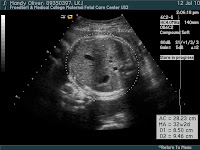

More Ultrasound Pictures

I went in to have another ultrasound last Monday so that they could measure little Wesley and estimate his weight. He weighed 6 pounds 4 ounces which is a little small, but still a good birth weight.Although I have a few more weeks so hopefully he puts on some more. The doctor has been doing non-stress tests on him every week I've gone in and his heart is really strong and he's an active fellow so she's not worried about him being under any stress. I'm hoping he comes soon because Mitch is off of school for the next two weeks and his help would be great! But if he doesn't come by then that's ok too, as long as he's healthy, I'll be happy. These are some cute pictures that the ultrasound tech got of Wesley's little face. A little creepy but you have to remember they are in 2-D not 3-D so your missing some levels there that would make it look a little less odd. We can't wait to you get here baby Wesley..jpg)

Pyelectasis, Ultrasounds & Contractions

So baby Wesley has had some problems with his little kidneys being a little dilated so I've had to go in and get some extra ultrasounds done to see if there has been any change. All the measurements were "ambiguous" (which was the doctors favorite word every time we went in there) meaning they didn't say either way if it was above normal or if it was in fact getting better, so I went back for three ultrasounds to keep checking. On the last one because I am so close to my due date and the measurements were still "ambiguous", they are going to have little Wesley come in a little while after he is born to see what's happening. Here is some information about Pyelectasis if you'd like to learn more about it, if not skip down to the ultrasound pictures.

These are some really cute profile pics. I love the one of him sucking his thumb..jpg)

Here are a couple shots of the kidneys. The two black areas in the middle of the white circle are his kidneys..jpg)